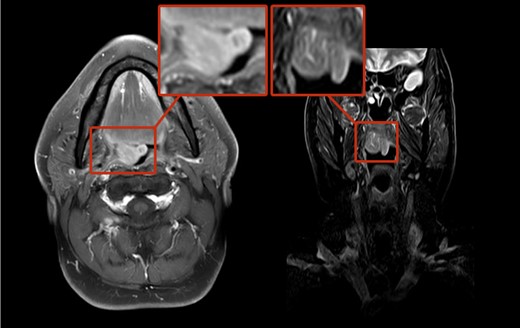

A 65-year-old male was referred to our department with a constant urge to clear the throat for a time span of 12 months. In addition, the patient stated his progressing inability to swallow food. Due to these symptoms, a resection of the thyroid gland had been carried out earlier showing struma colloides nodosae as well as bilateral parathyroidal adult rhabdomyomae. Even so, there was no relief in symptoms. At outpatient presentation at his dentist, a slight swelling of the soft palate was felt and the patient was referred for further therapy. Endoscopic examination as well as magnetic resonance imaging (MRI; Fig. 1) unveiled a tumor on the right side of the soft palate with a size of 5 × 5 cm2 and distinct demarcation to the surrounding tissue. Subsequently, the lesion was completely excised (Fig. 2) and histopathological analysis was conducted that showed a circumscribed but not encapsulated mesenchymal tumor with polygonal cell formation. The cells presented a granular cross-striated eosinophilic cytoplasm, large round vesicular nuclei and so called spiderweb cells (Fig. 3). Immunohistochemically, the cytoplasm of the cells was 100% positive for antibodies to desmin and S100 (Fig. 4). Additional immunohistochemical markers showed slight nuclear positivity for myogenin and nuclear negativity for AE1/3, CD68 as well as melan A. The histological examination confirmed ARM without signs of malignancy. At a total follow-up of 3 years, including MRI scan, no signs of recurrence were detected.

ER can be classified in fetal rhabdomyoma (FRM), adult rhabdomyoma (ARM) and genital rhabdomyoma (GRM). ARM are more common in male than in female (ratio 4:1) and usually found in the head and neck region (~90%) but they can be found in extremities as well. The mean age at the time of diagnosis is 50 years. Typically, ARM are solitary tumors which can occur multinodular in the same anatomic region [3, 4]. The first clinical signs of ARM are globus sensation, hoarseness, soft painless slow growing mass, dysphagia or other symptoms related to the location of the tumor in the aerodigestive tract. In CT scans, EARM can be misinterpreted as malignant tumors because of their indistinct borders blending into adjacent isodense muscles while presenting itself as slightly hyperdense homogenous lesions. In T1- and T2-weighted MRI, the tumors are isointense or slightly hyperintense to muscle with a homogenous enhancement. Tumor FDG-uptake in (18) F-FDG PET/CT scans is increased and might be a more accurate diagnostic tool [5, 6] than CT and MRI scans. Additionally the use of (18) F-FDG PET/CT scans is good choice in order to ensure its complete removal. This approach can necessary in multilobulated forms of ARM that complicate a total excision [5]. Fine-needle biopsies are a good method for pretherapeutic diagnosis [7].